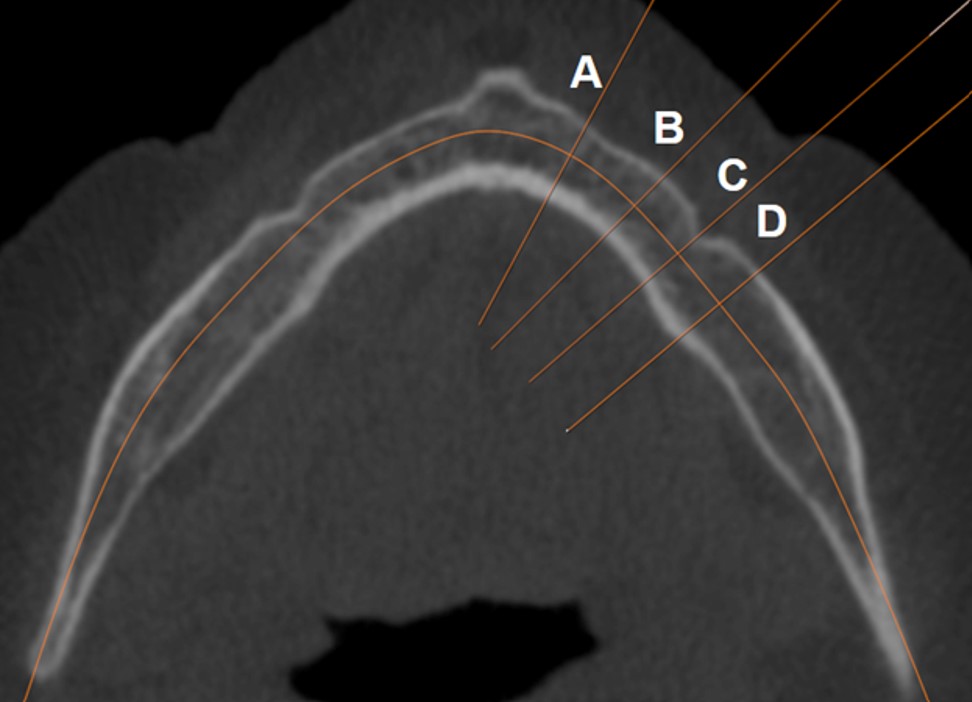

Ir apmācīts un validēts modulārs dziļais neirona tīkls, pamatā izmantota ResNet-101 arhitektūra. Tīkls sastāv no trim secīgiem dziļās apmācības modeļiem klasifikācijas un diviem regresijas uzdevumu risināšanai. Pirmais spēj atlasīt nepieciešamo apakšžokļa kaula griezumu KSDT attēlos aksiālā griezumā, kur vislabāk redzama foremen mentale. Tīkla apmācības precizitāte 98.85% (39 epohas), validācijas precizitāte 93.99% (35 epohas). Otrs veic apakšžokļa kaula griezumus pēc iepriekš definētiem attālumiem, iegūstot apakšžokļa šķērsgriezuma laukuma attēlus. Trešais veic apakšžokļa kortikālā kaula biezumu mērījumus.

Anda Slaidiņa prezentē 2023 Orālās veselības pētījumu kongresā, Grieķijā pētījumu, kura mērķis bija noteikt, cik lielā mērā apakšžokļa kortikālā kaulu biezums, kas iegūts no konusa staru datortomogrāfijas (KSDT) attēliem, ir saistīts ar kaulu minerālo blīvumu (KMB). Kā arī novērtēt, vai KSDT attēli var tikt izmantot osteoporozes riska prognozēšanai sievietēm pēcmenopauzes periodā.